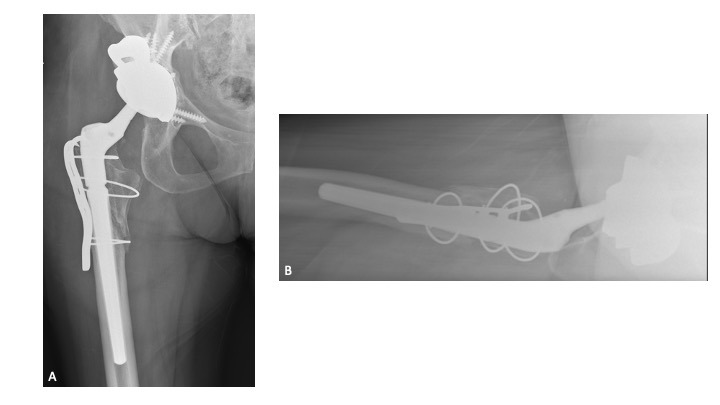

A 63-year-old female presented with recurrent THA instability - verbal consent was obtained for this report. She underwent L2-S1 posterior stabilization with L2-L3 anterior lumbar interbody fusion in May 2002 (Figure 1) and an uncomplicated right THA in April 2007. (Figures 2a-b) Five years following primary THA (July 2011), the patient sustained her first THA dislocation, which was treated with a closed reduction. Between 2011 and 2018, the patient had seven repeat episodes of hip instability – in 2012, one was complicated by a peri-prosthetic femur fracture requiring three revisions and reconstruction with a trochanteric claw plate. She was subsequently diagnosed with a prosthetic joint infection (PJI) which required an antibiotic spacer and subsequent re-implantation three months later. (Figures 3a-b) Following treatment of initial instability and femur fracture, the implants included a size 16 standard taper femoral stem and a 50-mm acetabular shell with 32-mm liner.

Twelve-weeks following re-implantation (2018), the patient experienced recurrent THA instability and was transitioned to our care for definitive treatment. At this time, the patient had a BMI of 24.22 kg/m2 and a past medical history of hypertension, rheumatoid arthritis, gastroparesis, hypothyroidism, and iron deficiency anemia. Relevant prescription medications included calcium carbonate, cholecalciferol, cyclobenzaprine, diltiazem, gabapentin, levothyroxine, and lisinopril. In August 2018, the patient underwent right THA acetabular revision with a porous titanium acetabular shell (56-mm) and dual mobility acetabular liner (44-mm), with four screws (30-mm x 2; 25-mm x 2) for adjuvant fixation. The existing stem was well-fixed and left in place, and a 44-mm/28-mm (+6) ceramic taper sleeve head was impacted. (Figures 4a-b) The patient followed a normal post-operative course and was ambulating pain free without assistance.